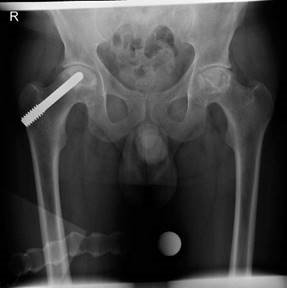

The left femoral head has a possibly minimal osteoporosis and/or blurring and poor definition of the bony trabeculae (Ficat 1). The radiograph is suspicious of bilateral AVN. I would like to obtain a frog-leg lateral radiograph of both hips. I would look for the crescent sign, indicating subchondral fracture, a feature of AVN that is more obvious on a frog-leg lateral than AP projection. This is because the anterior and posterior margins of the acetabulum on the AP projection are superimposed over the superior portion of the femoral head, the usual location of the sign. When AVN is bilateral, it usually occurs in each hip at different times, and the staging of disease in each hip is often different.

Figure 2.8 Anteroposterior (AP) radiograph of bilateral avascular necrosis.

In the second method, bone marrow obtained from the pelvis is centrifuged in the operating room to yield a bone marrow concentrate rich in stem cells. The patient is supine on a traction table with a C arm image intensifier. Percutaneous core decompression drilling with a Kirschner wire (diameter 2.7 mm) is performed to perforate the interface between the necrotic lesion and healthy bone. Following this concentrated autologous bone marrow aspirate is slowly transplanted into the necrotic area under fluoroscopic control. This is still an experimental procedure but early results seem promising for early disease. EXAMINER : The patient had surgery on both hips. These are his postoperative radiographs. CANDIDATE : The AP radiograph demonstrates a metal core rod in the right hip. (Figure 2.9.) EXAMINER : What do we call this? CANDIDATE : The patient has had a tantalum rod inserted into the femoral head. The implant achieves decompression, supports the subchondral plate of the necrotic areas and probably induces bone regeneration. EXAMINER : Anything else? CANDIDATE : The use of a trabecular metal ‘AVN rod’ has a number of attractive theoretical advantages, including no donor site morbidity, improved rehabilitation, structural support of the femoral head and the potential for

Figure 2.9 Anteroposterior (AP) radiograph pelvis with tantalum rod inserted into the right hip.